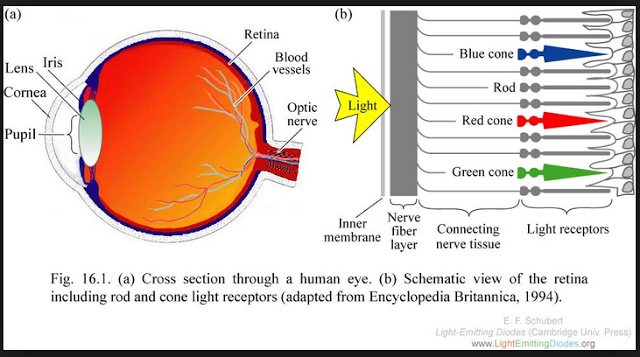

44 eye cones/rods software wars

…..COne ….. programming the human eyeball cones/rods

with possible schemes